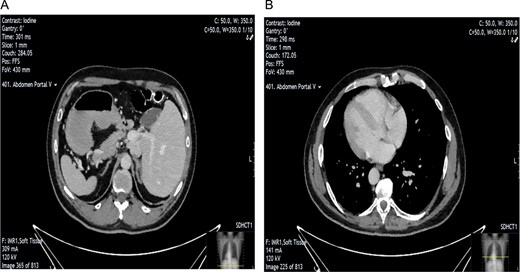

The patient was put under general anaesthesia and placed in the supine position. The operating surgeon and first assistant operating the camera stood on the patient’s right-hand side. The second assistant and scrub nurse stood opposite on the patient’s left. The laparoscopic stack and screen were positioned at the patient’s left shoulder. A 12 mm port was placed in the infra-umbilical position following open Hassan cut down, and pneumoperitoneum was achieved with CO2 at 14 mmHg and a flow rate of 5 LPM. One 11 mm port and two 5 mm ports were inserted under direct vision in an exact mirror image of a standard LC with normal anatomical positioning. This involved port placement as follows; 11 mm port in the subxiphoid area, 5 mm port in the left medial subcostal area, and a further 5 mm port in the left lateral subcostal area (Fig. 2). The patient was positioned with 30 degrees of head up and 20 degrees of left sided tilt. Upon insertion of the camera, it was imperative that we correctly orientated ourselves to the patient’s anatomy (Fig. 3).

Intra-operative image taken illustrating laparoscopic port setup.

In the case described by He et al., the main challenge faced by the right-hand-dominant operating surgeon was using their left hand for dissection, clipping the cystic artery and duct, and cutting these structures. Repeated examination and cross-checking of anatomy were key to ensuring safety during LC in SIT. A four-port approach was used, mirroring the exact setup of the standard LC (Fig. 2). During the dissection, the surgeon proceeded in the way they were comfortable, dissecting with the right hand and applying surgical tension with the left. This approach meant that the majority of the dissection was performed towards the midline, where our anatomical checkpoints were crucial. We ensured that our dissection was well above Rouvière’s sulcus.